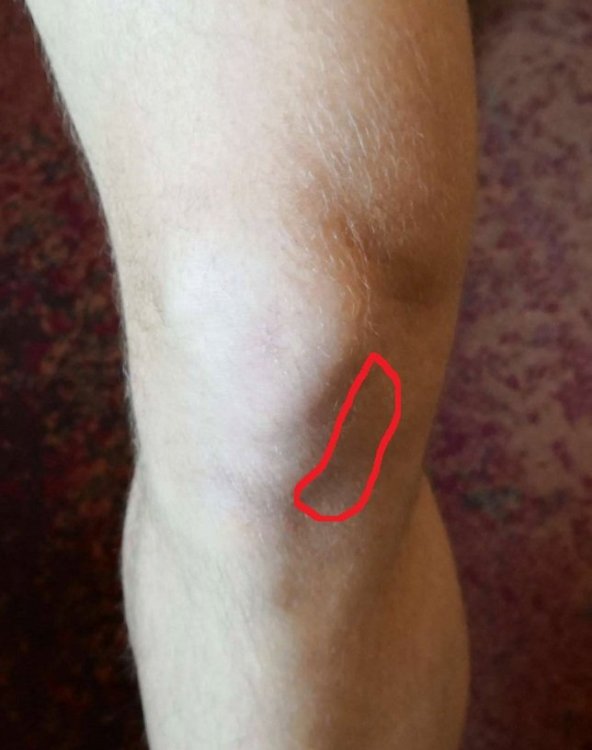

_GoGoL_ Napisano 13 Marca 2019 Napisano 13 Marca 2019 Cześć Sprawa wygląda tak. W 2017 miałem kontuzje kolana pod koniec sezonu koło września, przez jesień/zimę kiedy nie jeździłem, około 5-6 miesięcy uraz sie zagoił, ból przeszedł. Kiedy wsiadłem na rower w maju 2018 było cacy. Przejeździłem cały sezon, tylko tym razem sezon trwał dla mnie "non stop" bez względu na porę roku czyli innymi słowy jeździłem cały czas. Cały 2018 był OK, bez bólu, a kolano mocno zajeżdżałem, MTB/full i wszystko było super. Ból powrócił, tak naprawdę bez powodu w tym roku, 10 lutego podczas zwykłej wycieczki rowerowej. W tym samym miejscu bolesność co kiedyś. Efket? Panika bo wiedziałem ile ostatnim razem musiałem pauzować. Teraz jestem na dobrą sprawę "przed sezonem" wiosna/lato przed nami, a tu kontuzja A konkretnie wygląda to tak. Ból pojawia się TYLKO podczas ruchu pedałowania, wciskania pedałów w dół, innymi słowy przyspieszania. Zlokalizowany jest on po wewnętrznej stronie rzepki (zaznaczone na zdjęciu). Od 3 tygodni odpoczywam, nie forsuje kolana, nie jeżdżę na rowerze. Kilka dni temu wyszedłem sprawdzić czy coś się poprawiło - po 300m delikatny ból/dyskomfort w tym miejscu zaznaczonym na czerwono powrócił - wróciłem do domu. Na co dzień nie boli mnie wcale. Mogę normalnie funkcjonować. Miałem dziś robione USG tego kolana (zdjęcia w załącznikach opis/skan). Powiedzcie co robić? Jak leczyć "zdrowe" kolano? Ortopeda mnie już widział i póki co zlecił jedynie USG, które wykonałem. Czy spotkaliście się kiedyś z takim przypadkiem? Co byście sugerowali? Jakie kolejne kroki? Nie chcę być bierny i czekać miesiąc z nadzieją, że może samo przejdzie. Chce "zaatakować" temat i wyleczyć kolano najszybciej jak to możliwe. Info: Rower full, odpowiednio dobrana rama, geometria ok. Najbardziej oczywista kwestia to pozycja na rowerze, nie? Ale bądź tu człowieku mądry i zrób "bike fitting" na fullu, kiedy wysokość siodełka zmienia się cały czas względem pedałów.